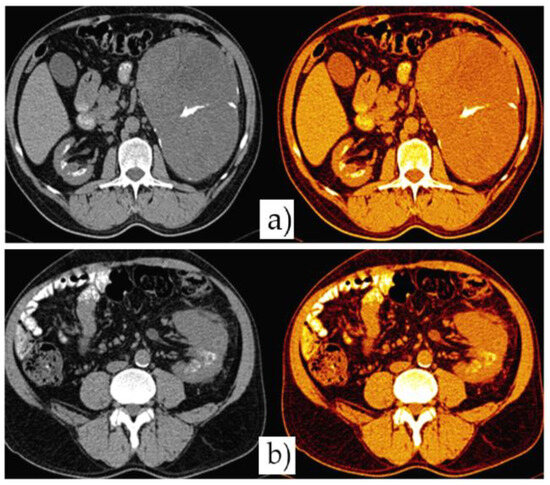

Due to the high level of creatinine presented, a native abdominopelvic CT scan was performed and the results were as follows: in the left hypochondrium and abdominal flank, a large mass was found, with an axial diameter of circa 182/136 mm and a craniocaudal diameter of approximately 212 mm, which is clearly delimited by its partially calcified walls and characterized by mainly fluid signal (including also tissue areas, septa and micronodular calcifications. The mass imprints and moves anteriorly and cranially the left postero-lateral parietal peritoneum, the spleen and the corporeo-caudal segment of the pancreas. It also imprints the regional enteric loops and the left colic flexure, being into contact through its posterosuperior pole with the left hemidiaphragm on which it discreetly ascends. The tumor seems to originate at the cortical level of the anterior valve of the left kidney, which is located in a lower position than normal. The CT scan also showed patchy calcifications arranged somewhat circumferentially at the level of both renal medullas, without obvious involvement of their cortex (nephrocalcinosis). The rest of the intra- abdominal organs had a normal appearance at the time of examination (Figure 3 and Figure 4).

Figure 4. Different color-coded axial sections of native Due to the high level of creatinine presented, a native CT scan showing large retroperitoneal mass. The mass seems to originate at the cortical level of the anterior valve of the left kidney, which is located in a lower position than normal.